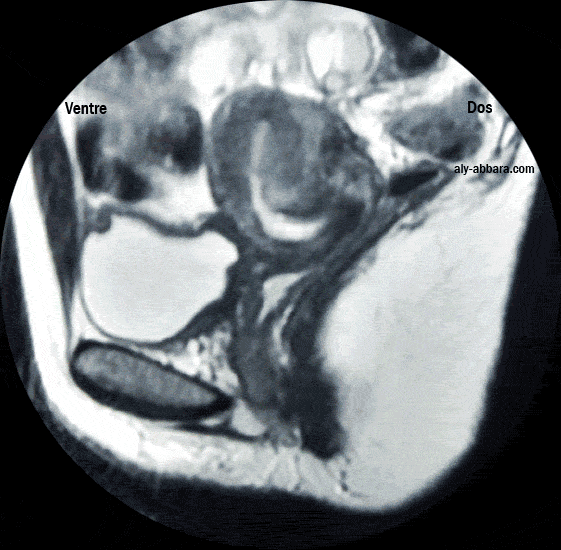

Utérus rétrofléchi, rétroversé identifiable par l'IRM

Utérus rétrofléchi rétroversé

(Imagerie par résonance Magnétique " IRM ")

• On parle de l'utérus rétrofléchi quand l'angle qui se forme entre l'axe du col de l'utérus et l'axe du corps

de l'utérus est ouvert en l'arrière vers le coccyx.

• On parle de l'utérus rétroversé quand l'angle que fait l'axe du corps de l'utérus avec un plan horizontal

passant par l'isthme est situé en arrière de ce plan, donc le fond de l'utérus se situe à arrière de ce plan.